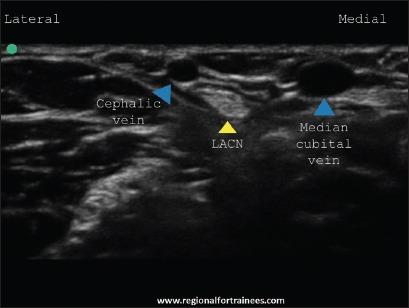

Upper extremity surgery is commonly performed under regional anesthesia. The advent of ultrasonography has made performing upper extremity nerve blocks relatively easy with a high degree of reliability. The proximal approaches to brachial plexus block such as supraclavicular plexus block, infraclavicular plexus block, or the axillary block are favored for the most surgical procedures of distal upper extremity. Ultrasound guidance has however made distal nerve blocks of the upper limb a technically feasible, safe and efficacious option. In recent years, there has thus been a resurgence of distal peripheral nerve blocks to facilitate hand and wrist surgery. In this article, we review the technical aspects of performing the distal blocks of the upper extremity and highlight some of the clinical aspects of their usage.

上肢手术通常在区域麻醉下进行。超声检查的出现使得进行上肢神经阻滞相对容易,且可靠性高。对于大多数上肢远端的外科手术,臂丛神经阻滞的近端入路,如锁骨上神经丛阻滞、锁骨下神经丛阻滞或腋路阻滞,是比较常用的。然而,超声引导使得上肢远端神经阻滞成为一种技术上可行、安全且有效的选择。近年来,远端周围神经阻滞因此再度兴起,以方便手部和腕部手术。在本文中,我们回顾了进行上肢远端阻滞的技术要点,并强调了其使用的一些临床方面。